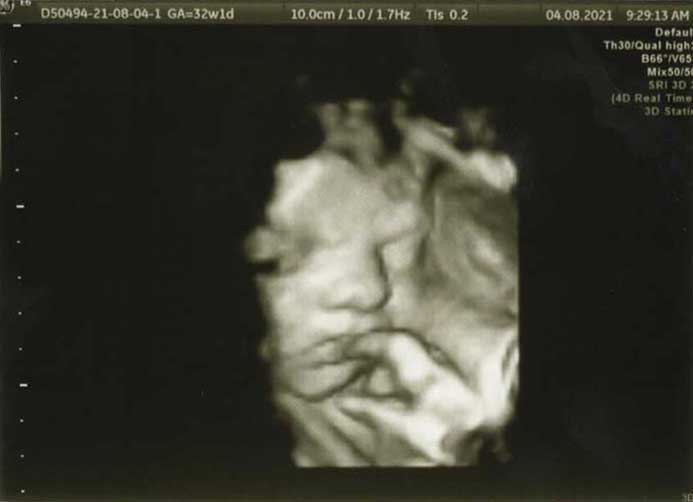

3D/4D HD LIVE

Στο ιατρείο μας προσφέρουμε υψηλής ευκρίνειας 3D και 4D τεχνολογία απεικόνισης του εμβρύου. Η τεχνολογία αυτή αποτελεί ένα ακόμα σημαντικό διαγνωστικό όπλο στη φαρέτρα του προγεννητικού ελέγχου, ενώ ταυτόχρονα ενισχύει την ανάπτυξη του δεσμού ανάμεσα στους μελλοντικούς γονείς και το μωρό τους.